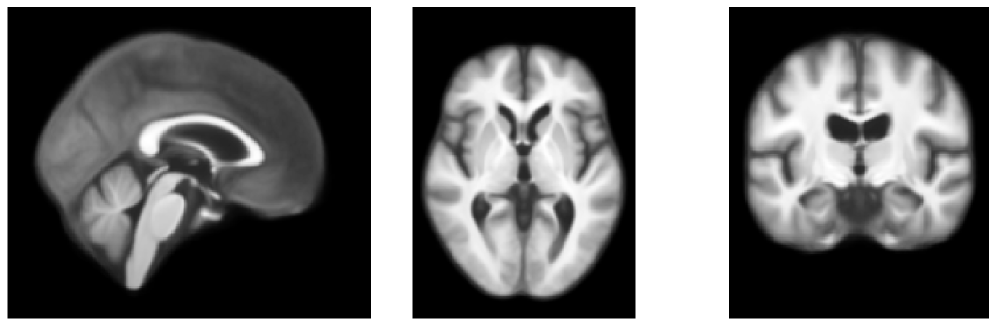

To better understand our dataset variability and estimate the visual difference/improvement for any downstream solution, we also compute and visually assess the template produced by averaging the first 100 subjects in our dataset without registration, but omit it from quantitative analysis as the quality is too low.

Figures 5 and 6 show visualizations for templates produced by AtlasMorph and the AtlasMorph-Uncond variants. Supplemental Figure 15, and Figure 16 show templates optimized using ANTs. The Aladdin templates are shown in Supplementary Figure 17 and Figure 18. The learned AtlasMorph templates are significantly sharper than the average of the population, shown in Figure 4.